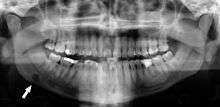

Dental Infection and Atherosclerosis

Atherosclerosis is attributed to risk factors that include cigarette smoking, hyperlipidemia, obesity, diabetes mellitus, and hypertension (high blood pressure). These factors, however, do not fully account for the risk of disease. Atherosclerosis has been conceptualized as a chronic inflammatory response to endothelial cell injury[21] and dysfunction possibly arising from chronic dental infection. In 2010, using the previously validated Mattila panoramic radiographic index to quantify the totality of dental infection (i.e., periapical and furcal lesions, pericoronitis sites, carious tooth roots, teeth with pulpal caries, and vertical bony defects), Friedlander’s group determined that individuals with carotid artery atheromas on their panoramic radiographs had significantly greater amounts of dental infection/inflammation than atherogenic risk-matched controls devoid of radiographic atheromas.[22][23] While the Mattila index had been previously used to relate the extent of dental infection to coronary artery disease, this research is the first to link the full range of dental disease that it measures to panoramic radiographs evidencing calcified carotid artery atherosclerosis.